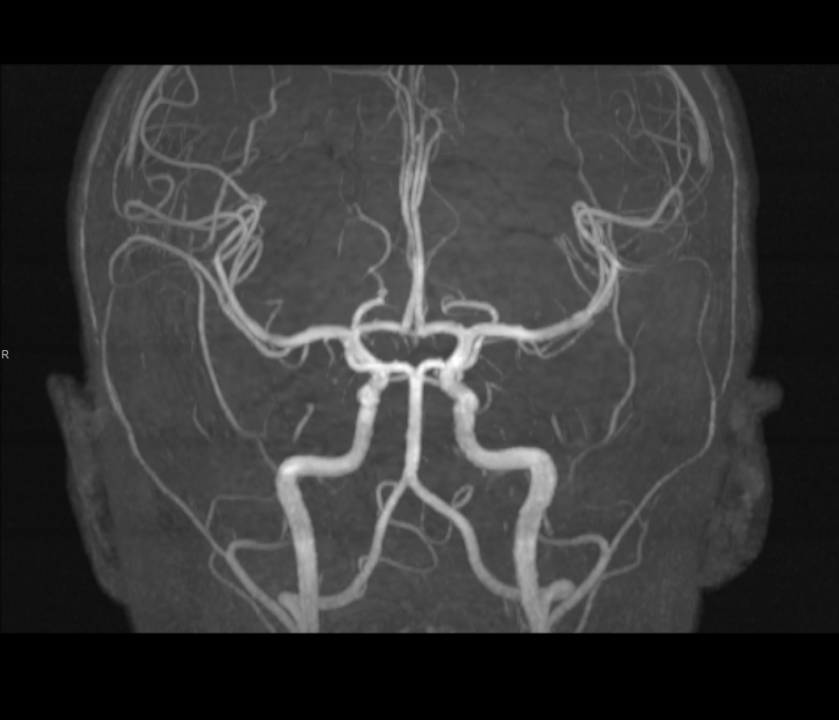

Tijekom Tjedna mozga Poliklinika Affidea Vita daje 20 posto popusta na magnetsku rezonancu!

Povodom obilježavanja Tjedna mozga od 11.

tjedan mozga

MR mozga

MR angiografija